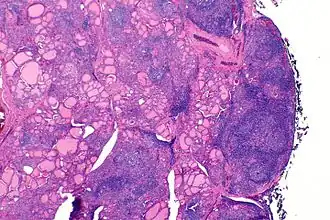

Аутоиммунный тиреоидит (тиреоидит Хашимото) — гистологическая картина

Аутоиммунный тиреоидит (тиреоидит Хашимото, АИТ, хронический аутоиммунный тиреоидит, лимфоцитарный тиреоидит; лат. morbus Hasimoti, thyreoiditis Hasimoti, struma lymphocytaria, struma lymphomatosa, struma autoimmunea, struma Hasimoti) — хроническое воспалительное заболевание щитовидной железы аутоиммунного генеза, при котором в результате хронически прогрессирующей лимфоидной инфильтрации происходит постепенная деструкция паренхимы щитовидной железы с возможным исходом в первичный гипотиреоз. Впервые заболевание было описано японским хирургом Х. Хасимото в 1912 г. Он наблюдал несколько случаев увеличения ЩЖ, обусловленного лимфоидной инфильтрацией (лимфоматозный зоб), в связи с чем термином тиреоидит Хашимото обозначают гипертрофический вариант АИТ, хотя очень часто его распространяют на хронический АИТ в целом.

Заболевание развивается на фоне генетически детерминированного дефекта иммунного ответа, приводящего к Т-лимфоцитарной агрессии против собственных тиреоцитов, заканчивающейся их разрушением. Гистологически при этом определяются лимфоцитарная и плазмоцитарная инфильтрация, онкоцитарная трансформация тиреоцитов (образование клеток Гюртле-Ашкенази), разрушение фолликулов. АИТ имеет тенденцию проявляться в виде семейных форм. У пациентов с повышенной частотой обнаруживаются гаплотипы HLA-DR3, DR5, В8. В 50 % случаев у родственников пациентов с АИТ обнаруживаются циркулирующие антитела к ЩЖ. Кроме того, наблюдается сочетание АИТ у одного и того же пациента или в пределах одной семьи с другими аутоиммунными заболеваниями - пернициозной анемией, аутоиммунным первичным гипокортицизмом, хроническим аутоиммунным гепатитом, сахарным диабетом 1 типа, витилиго, ревматоидным артритом и др.